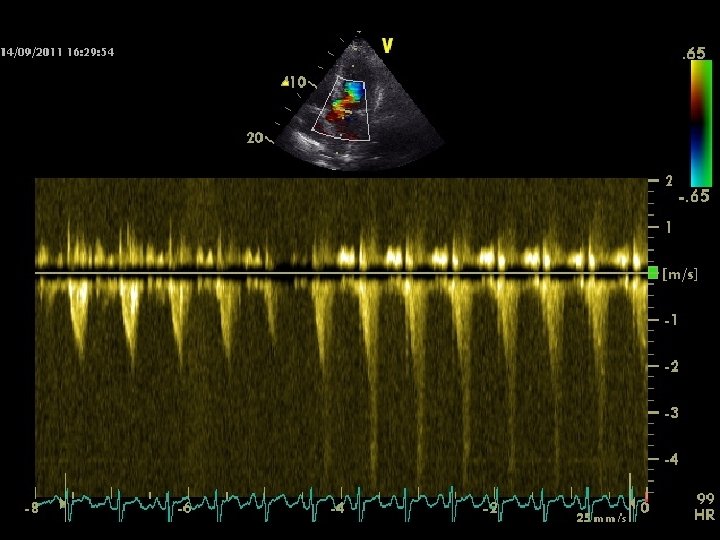

Valsalva Maneuver Decreased venous return & CO, HR ↑; PP↓ S 2 split narrows down, S 3 & S 4 diminish

Valsalva Maneuver • Reduces the intensity of all murmurs except that of HOCM & MVP • Murmur of HOCM intensifies as the LV cavity size decreases • Click occurs earlier, the murmur lengthens in MVP – may not intensify • During release, the intensity of right heart murmurs returns earlier - 1 to 3 vs 5 beats for left heart murmurs

VALSALVA STRAIN

ASD, HF, MS